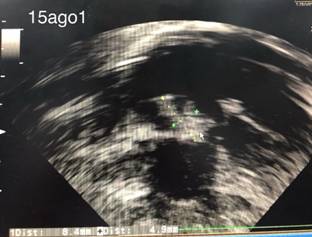

El diagnóstico se basa en datos clínicos, de imagen y microbiológicos.18 En todas las edades, el ecocardiograma es el estándar de oro para la identificación de la vegetación; en la mayoría, la ecocardiografía transtorácica es suficiente, pero a veces la transesofágica puede ser de utilidad. La Figura 1 muestra el caso de una vegetación de 8.4 x 4.9 mm de nuestra institución en el que se cumplieron los dos criterios mayores para hacer diagnóstico definitivo. Recientemente se ha descrito la utilidad de la tomografía por emisión de positrones, en particular en las endocarditis relacionadas a cardiopatías congénitas.19

Figura 1: Vegetación de 8.4 x 4.9 mm en válvula tricúspide en neonato de 29 semanas de gestación (35 corregidas).